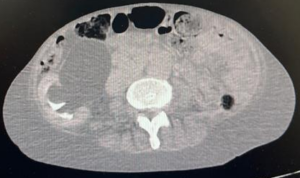

Paciente feminina, 68 anos, negra, que vive com HIV há cerca de 18 anos em tratamento irregular estava internada em unidade hospitalar para investigação de neoplasia linfoproliferativa e durante investigação foi solicitada tomografia computadorizada de abdome e pelve (relato de grande ureterohidronefrose direita e provável compressão ureteral extrínseca ao nível dos vasos ilíacos, com eliminação de contraste do ureter esquerdo em fase tardia), sendo pedido parecer a urologia.